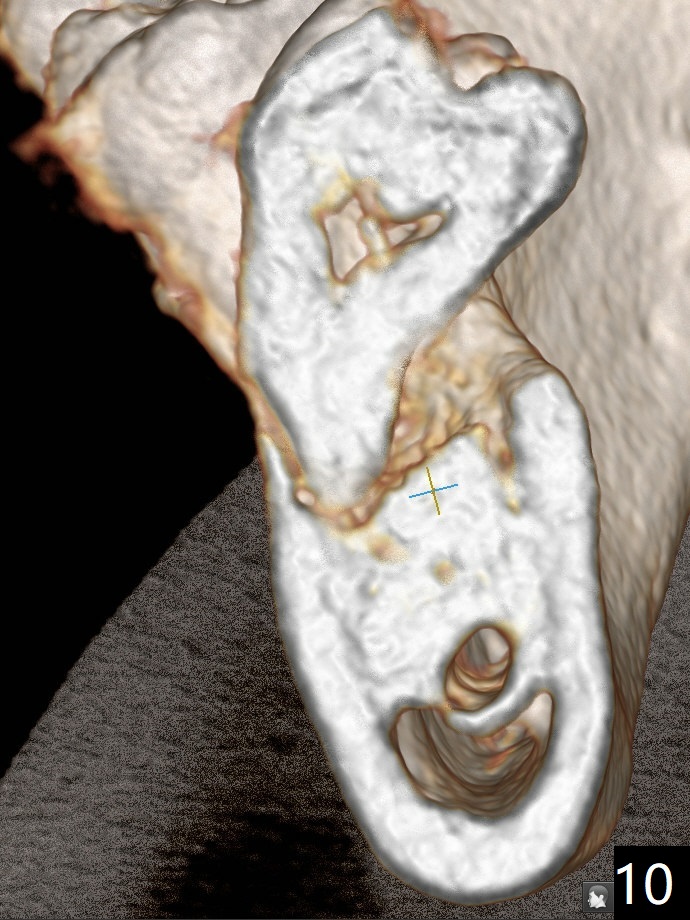

A 44-year-old woman has severe chronic periodontitis. The tooth #18 is nonsalvageable (Fig.1). To avoid distal end guide, do not remove the 3rd molar in the lab. While a 5x7.3 mm implant is long for the site (Fig.2), a 5.5x5.5 mm one seems to be a better option (Fig.3). The latter could be 1 mm more coronal. The last drill (5.0 mm) and cortical tap will be used free hand. #17 will be extracted after implantation. Since the patient is reluctant to have #16 to be extracted, place #18 implant ~ 1-2 mm more distal so that the implant crown will have some occlusal contact with #16. Prepare IS extra wide kit. Or use a 8/7 mm trephine bur to harvest cortical bone from the ramus. Drill a hole for fixation screw before removing the onlay graft. Keep the 3rd molar if possible. Prepare Tatum spacers to measure the size of #18 socket opening. In fact, the lab is able to place a 5x7.3 mm implant with 2 thread exposure buccal. Prepare sticky bone and PRFx2 to prevent periimplantitis. Soak one O-ring in case of having to extend osteotomy by .5 mm (next longer drill (1.5 mm) - 1 mm (O-ring)). For socket shield at #18 (Fig.6 *), section the tooth horizontal with a new surgical fissure bur (Fig.4 black area), use an end-cutting bur to remove buccal edge of the root (Fig.5 red area) and finally remove the lingual portion of the root (Fig.6 pink). Insert 4.5x10 mm dummy implant to determine whether the final implant 5x7.3 mm (bottom of the 1st line) will probably contact the shield. Buccal view of the lingually inclined 2nd molar (Fig.7). After removal of the crown of the 2nd molar (Fig.8 occlusal view), the lingual portion of the root is resected (Fig.9 black area). CT coronal sections show socket shield formation (Fig.10,11).